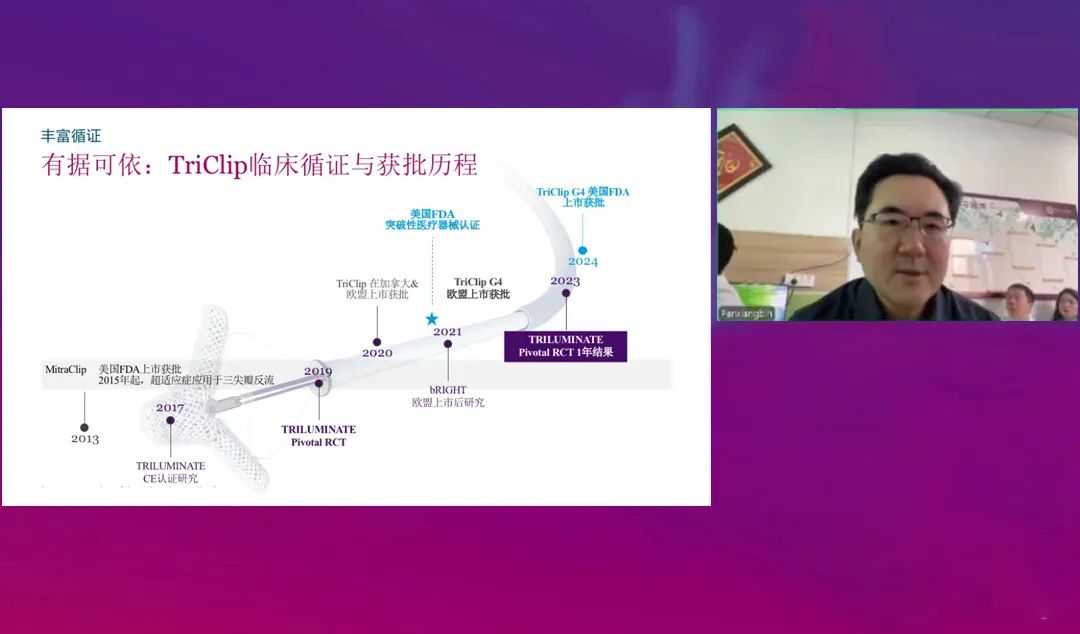

潘湘斌教授:TRILUMINATE Pivotal研究1年结果